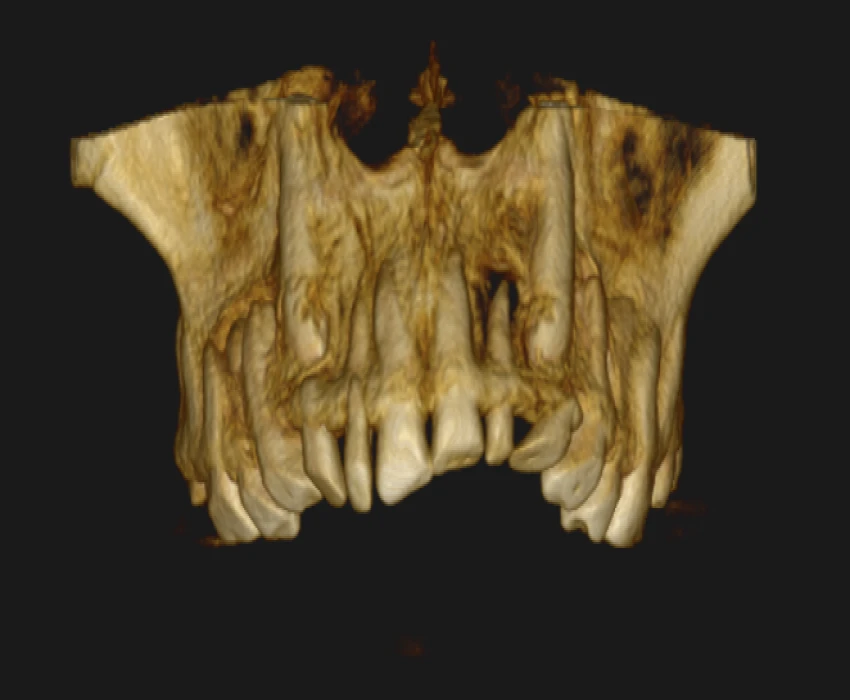

On intra-oral examination generalized loss of cervico-occlusion height and colour of the teeth appeared opalescent and brown in colour.

On the basis of history, clinical examination, and radiographic investigation final diagnosis was given as Amelogenesis imperfecta- Hypoplastic Type.

In patients with hypoplastic amelogenesis imperfecta, the basic alteration centers on inadequate deposition of enamel matrix. In the generalized pattern, pinpoint-to-pinhead–sized pits are scattered across the surface of the teeth and do not correlate with a pattern of environmental damage. The buccal surfaces of the teeth are affected more severely. Both dentitions, or only the primary teeth, may be affected. All of the teeth may be altered, or only scattered teeth may be affected.